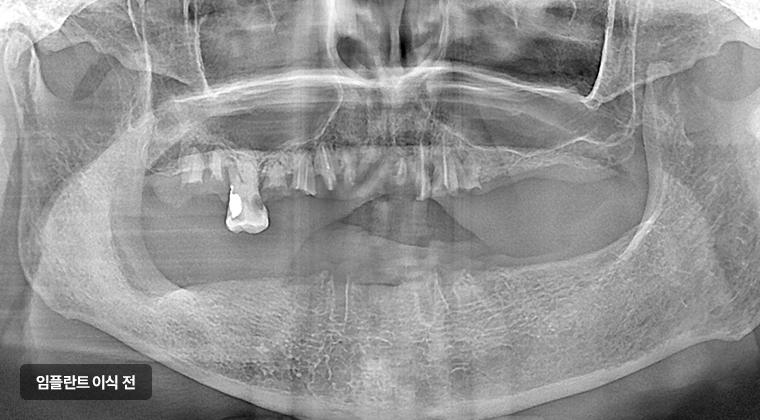

살릴 수 있는 치아가 거의 없는 경우,

전체 치아를 발치하고 임플란트로 진행하는 걸 말합니다.

보통 충치나 잇몸 염증이 심하신 분,

틀니 쓰시던 분들이 많이 진행하는 치료입니다.

전체 임플란트 식립 예시